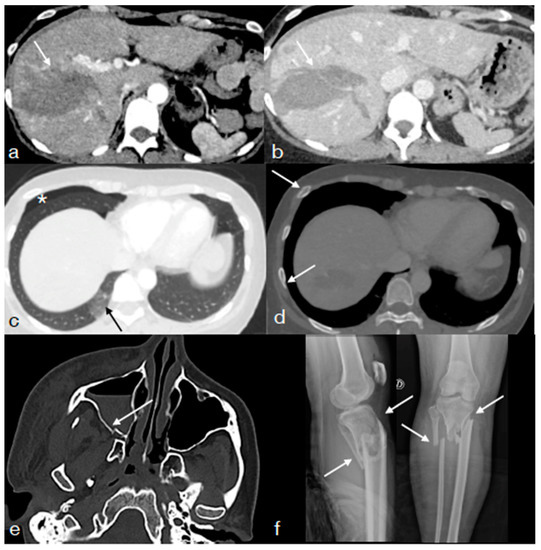

- Iacobellis, F.; Di Serafino, M.; Brillantino, A.; Mottola, A.; Del Giudice, S.; Stavolo, C.; Festa, P.; Patlas, M.N.; Scaglione, M.; Romano, L. Role of MRI in early follow-up of patients with solid organ injuries: How and why we do it? Radiol. Med. 2021, 126, 1328–1334. [Google Scholar] [CrossRef] [PubMed]

- Miele, V.; Piccolo, C.L.; Sessa, B.; Trinci, M.; Galluzzo, M. Comparison between MRI and CEUS in the follow-up of patients with blunt abdominal trauma managed conservatively. Radiol. Med. 2015, 121, 27–37. [Google Scholar] [CrossRef] [PubMed]